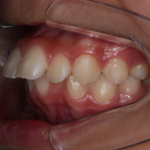

反対咬合(受け口)の症例

Before After 治療途中の小児矯正の症例です。 成長期に上顎の幅を広げ ...